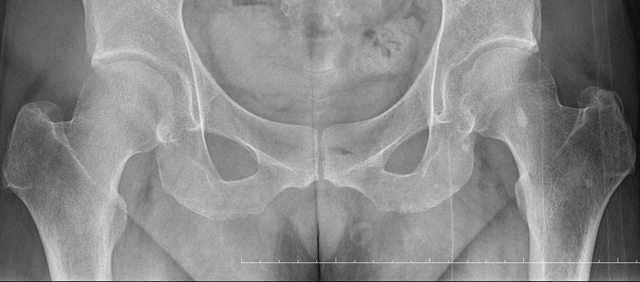

骨盆 https://i.imgur.com/h7KknkX.png

股骨頭放大特寫...左邊是右股骨 你覺得哪邊比較正常? https://i.imgur.com/16erxqZ.png

看了下治療方法,那有看等於沒看了 照MRI似乎也是白做,自費照根本浪費 其實X光以我外行人放大好幾倍看過去,左股骨跟大腿骨明顯狀態較差 不清楚醫生是不是有鷹眼,小小一張看過去就說沒什問題 我是不會去考慮手術的 小時候骨折都是看國術館 還減壓股頭打孔...開刀100%NO 治療方法 1.拐杖 2.藥物治療(1)非類固醇類消炎止痛藥(NSAID) (2)口服雙磷酸鹽類藥物 (3)血管擴張劑 (4)高壓氧 目前股骨頭缺血性壞死的治療,根據現有的證據,仍然以手術為主流。 於早期(第一、二期),尚未塌陷的股骨頭缺血性壞死,髖關節減壓手術值得一試, 至於第三、甚至第四期股骨頭缺血性壞死,人工髖關節置換術能夠有效的解除疼痛以及恢 復行走負重的功能。 ※ 編輯: capybaradash (118.166.44.25 臺灣), 07/31/2023 16:04:20

g17321732: 1.骨頭看起來沒大問題,x光不是放大找不一樣這麼簡單 07/31 18:18

g17321732: 3.MRI對你的幫助不大,X光已經足夠清楚,不用花冤枉錢 07/31 18:18

UCCUplz: 哪裡看起來壞死? 07/31 19:52

yasmine1030: 人體不是百分百對稱我實在看不出你X光兩邊股骨有何差 08/01 01:29

yasmine1030: 異 08/01 01:29